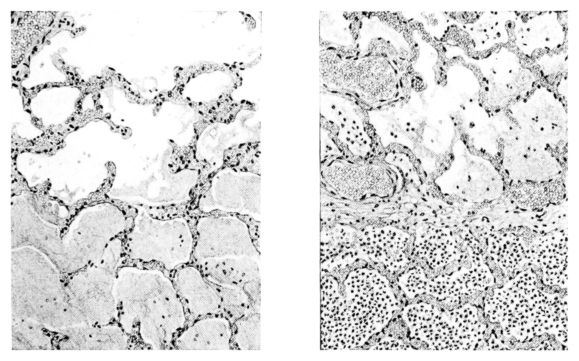

FIG. III. AUTOPSY NO. 90. DRAWING FROM A LESION OF THE TRACHEA (SOMEWHAT OLDER THAN THAT ILLUSTRATED IN FIGURE II). THE MUCOSA IS ENTIRELY LACKING. CONGESTION AND EDEMA ARE THE STRIKING FEATURES IN THE SUBMUCOSA. THE NECROTIZING PROCESS HAS EXTENDED INTO THE MUCUS GLANDS. THIS IS SHOWN IN THE LOWER PICTURE.

FIG. IV. AUTOPSY NO. 205. CONGESTION AND EDEMA OF THE SUBMUCOSA AND REGENERATION OF THE TRACHEAL EPITHELIUM.

The changes are less marked, perhaps, in the trachea than in its finer ramifications. The mucosa is constantly more or less destroyed and large areas, usually focal, are entirely devoid of their epithelial covering. This is replaced by a sparse exudate, composed largely of red blood cells, mucus, a small amount of fibrin, and nuclear fragments (Fig. II). It may dip into the submucosa for a short distance, but usually these indentures are associated with the ducts of the mucous glands into which the inflammatory reaction extends. A more striking feature than the exudate, however, is the edema and the congestion of the submucosa. The loose areolar tissue of the submucosa is spread widely apart, and throughout it distended blood vessels are very conspicuous. Occasionally such a vessel is broken and actual hemorrhage appears in the submucosa. Occasionally, too, the inflammation extends down the duct to the mucous gland itself, and here, also, aplastic inflammatory reaction is evident, inasmuch as the acini now stain intensely red with the cells undifferentiated from each other and specked here and there by broken remains of the dead nuclei (Fig. III). After the disease has continued for a short period, even at the end of five or six days, some regeneration of the epithelial lining may be seen (3) (Fig. IV). But despite this, the acute picture persists, and there goes on, side by side, an attempted repair characterized by epithelial regeneration and the same evidence of acute change. Since the lesion is essentially a superficial one, scars or contractures of any extent are not encountered in the trachea, even in examples of the disease that have ended fatally only after many weeks.[4]